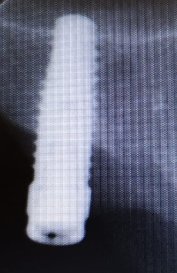

¿Alguien conoce la marca de este implante dental? Muchas gracias !!

Conexión octógono interno de 2’5mm con plataforma de 4’4mm

Sabéis q implante es ? Tiene una plataforma externa circular .

Hola!, El paciente me indica que se puso estos implantes hace unos 30 años en una clinica de Madrid centro... Alguna idea de marca y modelo ? Muchas gracias [...]

Buenas tardes, muchas gracias por vuestra labor, creo que estos dos implantes son eckerman all spiral, me podríais ayudar respecto a la plataforma y compatibilidades?? saludos